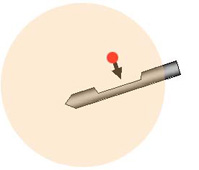

乳房をマンモグラフィで撮影し、位置決めをします。皮下と乳房に局所麻酔をします。これによりほとんど痛みを感じることはありません。病変をマンモグラフィで見ながら、乳房に針を刺入し組織を採取します。

2. 吸引